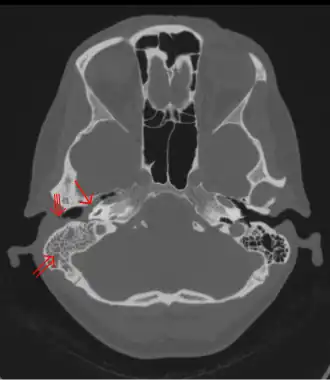

Computertomographie: Otitis media (einfacher Pfeil) und Mastoiditis (Doppelpfeil) der rechten Seite (linke Seite im Bild). Der äußere Gehörgang ist teilweise mit Eiterung besetzt (Dreifachpfeil). 44-jährige Frau.

Typisch für die Mastoiditis ist die neuerliche Zunahme der Ohrenschmerzen bei einer akuten Mittelohrentzündung nach anfänglicher Besserung oder die unveränderte Fortdauer der Beschwerden über die dritte Krankheitswoche hinaus. Der eitrige Ausfluss aus dem Gehörgang bleibt bestehen oder tritt wieder auf und das Trommelfell zeigt unverändert eine Verdickung und Rötung. Die Druckempfindlichkeit hinter dem Ohr und eine Senkung der hinteren oberen Gehörgangswand machen die Diagnose sicher, eine Schwellung hinter dem Ohr mit Abstehen der Ohrmuschel lassen keinen Zweifel mehr zu. Eine Röntgenaufnahme und insbesondere die Computertomographie zeigen einen knöchernen Destruktionsherd.